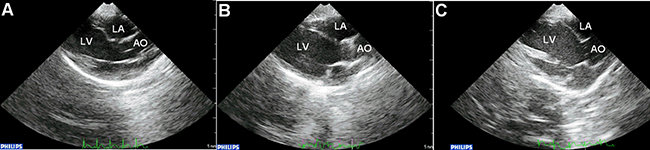

No significant differences in systolic and diastolic blood pressures, or in left ventricular end-point pressure were observed between controls, diabetes group alone and diabetes group with apocynin treatment (Table 2). Representative echocardiographic images in the parasternal long axis view are shown in Figure 1. Left atrial antero-posterior diameter, interventricular septal thickness and left ventricular posterior wall thickness were significantly increased in the diabetes group (P < 0.05). Increases in the latter two parameters were attenuated by apocynin treatment (P < 0.05). No differences in left ventricular end-diastolic or end-systolic diameters or in left ventricular ejection fraction were observed (P > 0.05).

Figure 1: Representative parasternal long-axis echocardiographic views in the control (A), diabetic group (B) and apocynin treatment group (C). Abbreviations: LA = left atrium; LV = left ventricle; AO = aorta.